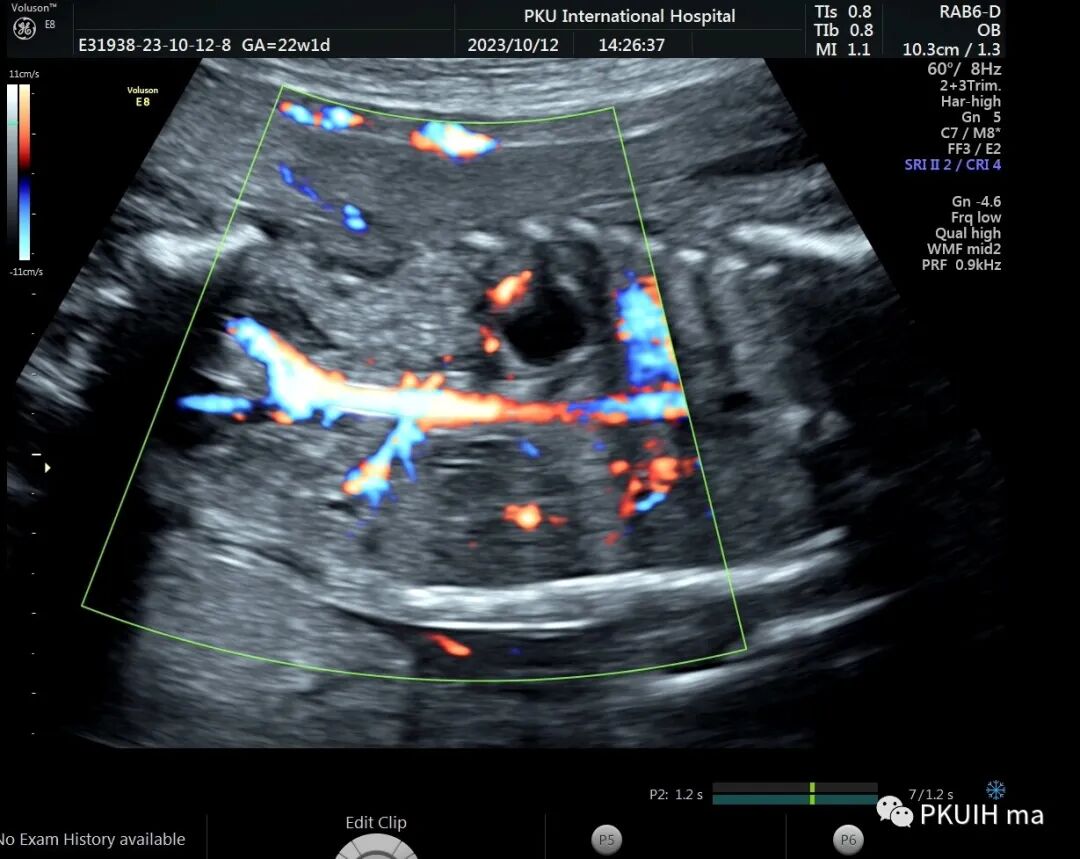

右肾大小位置正常,右肾动脉可见,左肾动脉缺如,正常的左肾区未见肾组织回声,可见肾上腺平卧。于膀胱后上方见一肾组织回声,大小约1.5x1.4x1.0cm,皮髓质分界欠清晰,血供来源于髂动脉。

异位肾较常见,发生率约1/1200,目前产前确诊并不困难。异位肾最常见的就是盆腔异位肾,占异位肾的一半以上,往往合并发育不良。血供可来源于腹主动脉或髂动脉,部分可有血管迷走。超声诊断标准:1、一侧肾区内未见肾组织回声;2、同侧的肾上腺呈平卧征;3、对侧肾可增大也可正常;4、盆腔可见一发育不良或发育正常的肾脏回声;5、可合并其他畸形,比如输卵管发育畸形或者是Vacterl综合征。